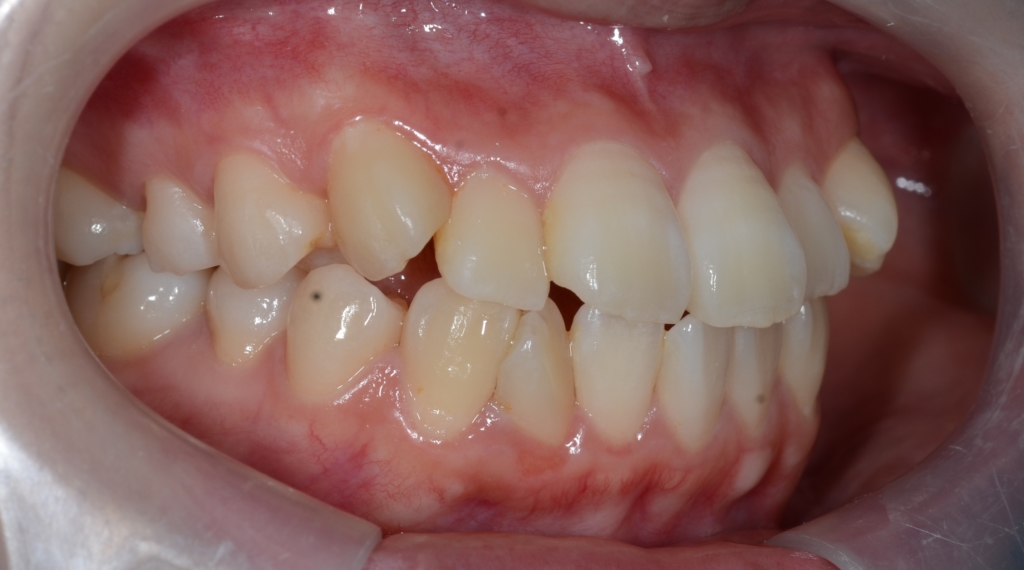

【Before】

#1.歯と顎の不調和による叢生(軽~中等度)

と診断しました。

【治療方針】

1.上下左右の奥歯を1本ずつ抜歯してスペースを作り、前歯の乱れを改善

2.残りのスペース分を使い、上下前歯を可及的に後方へ移動